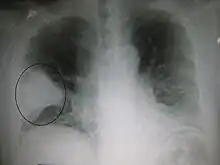

| A chest X-ray showing a very prominent wedge-shape bacterial pneumonia in the right lung | |

Normal lateral CXR AP CXR showing left lower lobe pneumonia associated with a small left sided pleural effusion

AP CXR showing left lower lobe pneumonia associated with a small left sided pleural effusion AP CXR showing right lower lobe pneumonia